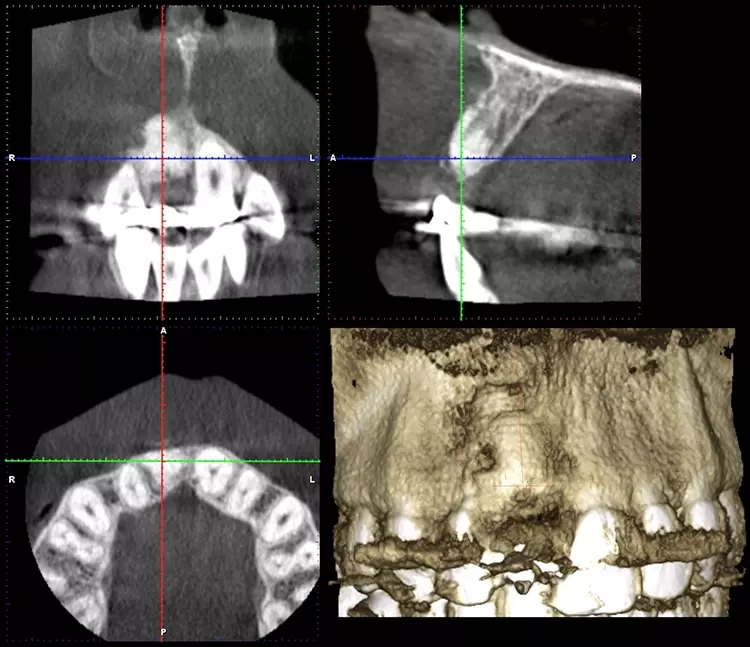

Im Sinne eines Backwardplanning wurde anhand eines Waxups die Marylandbrücke als auch die entsprechende Bohrschablone hergestellt. Nach eingehender präimplantologischer Diagnostik mittels Modellanalyse und digitalem Volumentomogramm (DVT) zeigte sich eine ausgeprägte bukkale knöcherne Fenestration (Abb. 8 und 10).

Zahnklinik Bochum

Nach einer viermonatigen Einheilzeit wurde im Rahmen der präimplantologischen Diagnostik ein DVT zur Überprüfung des Augmentationsergebnisses erstellt und die Implantatgröße festgelegt (Abb. 9 und 11). In Lokalanästhesie und unter Zuhilfenahme einer Bohrschablone erfolgte nach midkrestaler Schnittführung unter Schonung der Papillen die manuelle Insertion eines Straumann Bone Level Implantats mit den Maßen 4,1 x 10 mm RC (Straumann AG, Basel, Schweiz). Das Eindrehmoment betrug 35 Ncm.